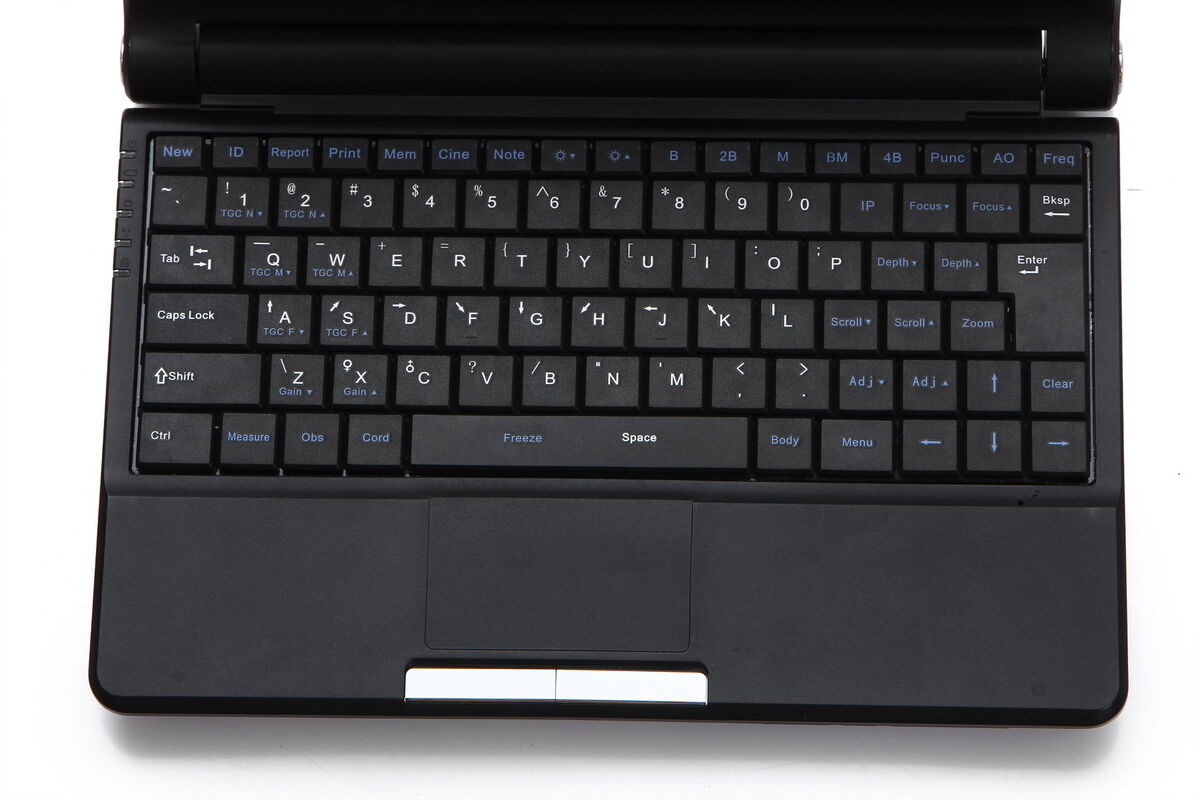

In terms of portability, the Medical Laptop Machine Ultrasound Scanner excels because it combines practicality with advanced technology. Its compact design and lightweight build allow easy transportation, so it can be taken to various locations—whether it’s a rural clinic or a home visit. The user-friendly interface and easy-to-navigate controls ensure that the device can be used effectively by medical professionals with varying levels of technical expertise. Because it operates on a rechargeable battery, it can be used almost anywhere, providing vital imaging services in situations where other equipment might be impractical.

This ultrasound scanner is designed with the user in mind. It offers a clear and bright display, so images can be viewed in great detail. The touch-screen functionality ensures intuitive operation, making it easier for professionals to focus on patient care rather than struggling with complex machinery. Additionally, it comes with multiple connectivity options, so transferring data and images to other devices or systems is seamless and straightforward.